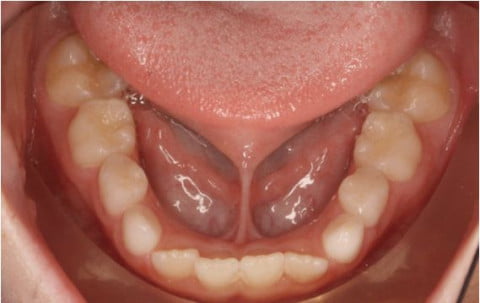

Dính phanh lưỡi ( thắng lưỡi ) là hiện tượng lớp màng mỏng nằm phía dưới lưỡi bị ngắn, dày và căng khiến chuyển động của lưỡi bị hạn chế

Làm mất thẩm mỹ của răng vì khi dính thắng lưỡi. Răng cửa hàm dưới thường bị nghiêng hoặc tạo ra khe thưa giữa 2 răng cửa.